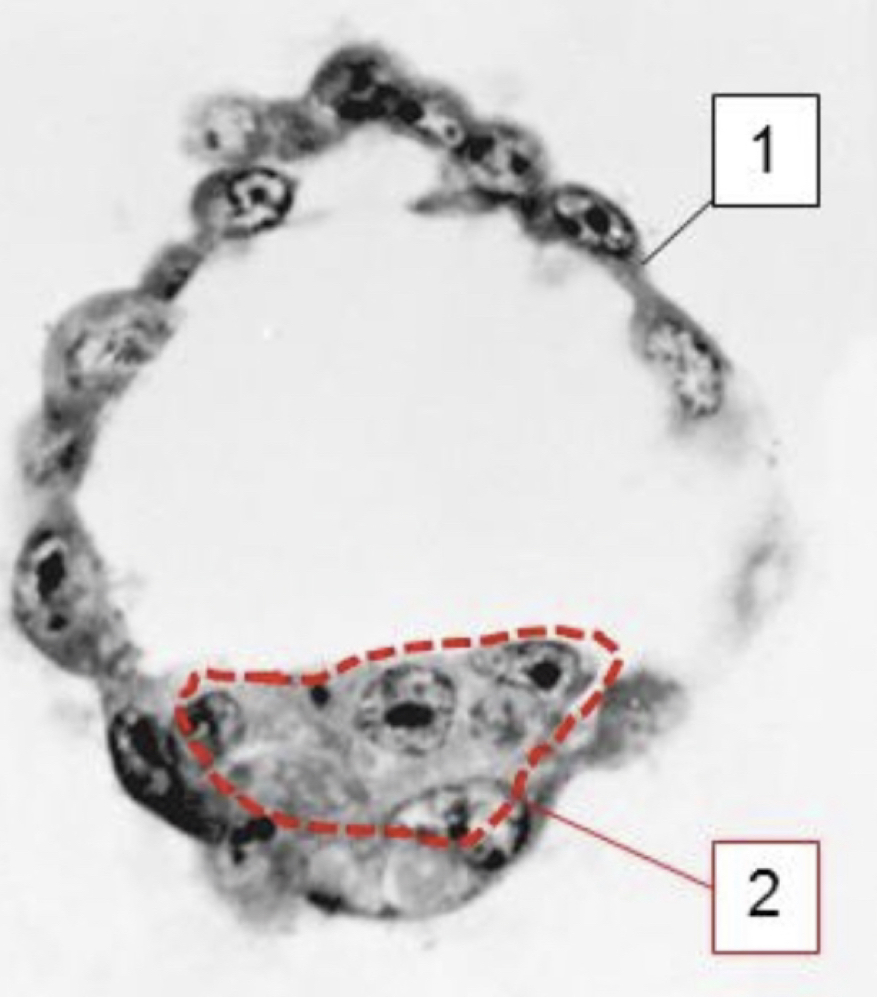

Benoem de vier structuren

In de 3e week na conceptie ontwikkelt het menselijk embryo zich tot een ellipsvormige schijf. De schijf bestaat oorspronkelijk uit 2 lagen, maar gedurende week 3 wordt een derde laag aangelegd. Dit proces heet de gastrulatie.